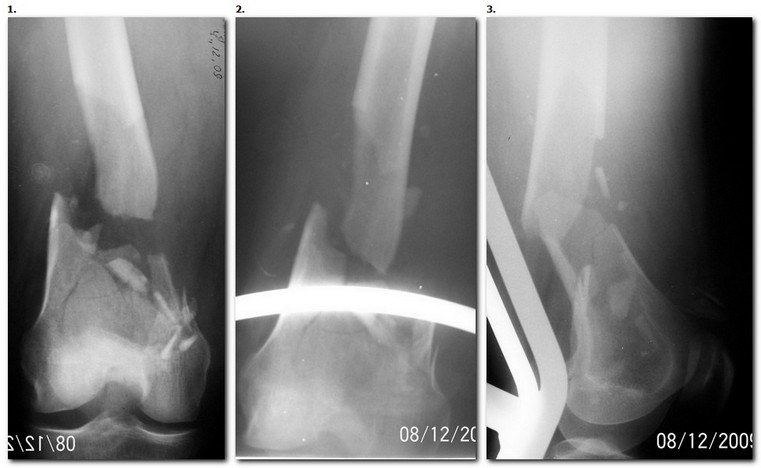

1. Открытый с дефектом кости 5 см оскольчатый внутрисуставной перелом дистального эпиметафиза бедренной кости. Величина дефекта установлена после сравнительных рентгенограмм обоих бёдер с линейкой. При поступлении выполнена ПХО раны, скелетное вытяжение за бугристость большеберцовой кости.

2. После долгих сомнений выполнена открытая репозиция перелома эпифиза бедренной кости, закрытый блокированный интрамедуллярный остеосинтез (к слову, оперативное вмешательство выполнено без применения ЭОПа). Предполагалась через 8 недель пластика костного дефекта спонгиозным аутотрансплантатом.

3. Снимок через 10 недель после операции. Имеется облаковидный регенерат. Решено от костной пластики воздержаться.

4. Через 6 месяцев имеем сросшийся перелом.

Уважаемые коллеги, прооперирована пациентка антеградным штифтом Остеомед, костная пластика не проводилась. Выбранный штифт по каналу бедренной кости на фоне отсутствия переднего кортикала в канале не центрируется. Технически неприятно, отсутствие передней и внутреннебоковой стенки до зоны мыщелков сильно затрудняло репозицию. Получилась вот такая картина. После стабилизации - очевидное повреждение ПКС и боковая нестабильность. В общем и далее будет чем заняться. Нам и в дальнейшем будет очень интересно мнение коллег.